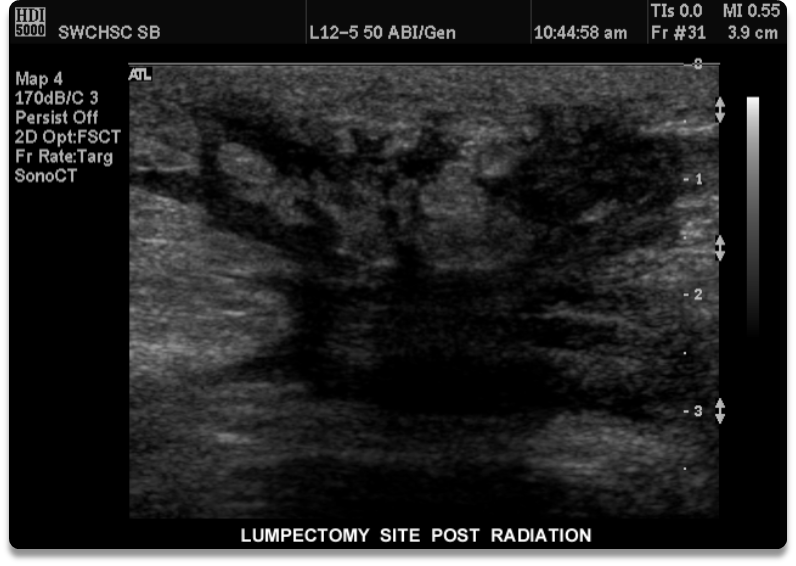

What is this image showing

a lumpectomy scar

What is this image showing?

lumpectomy post radiation